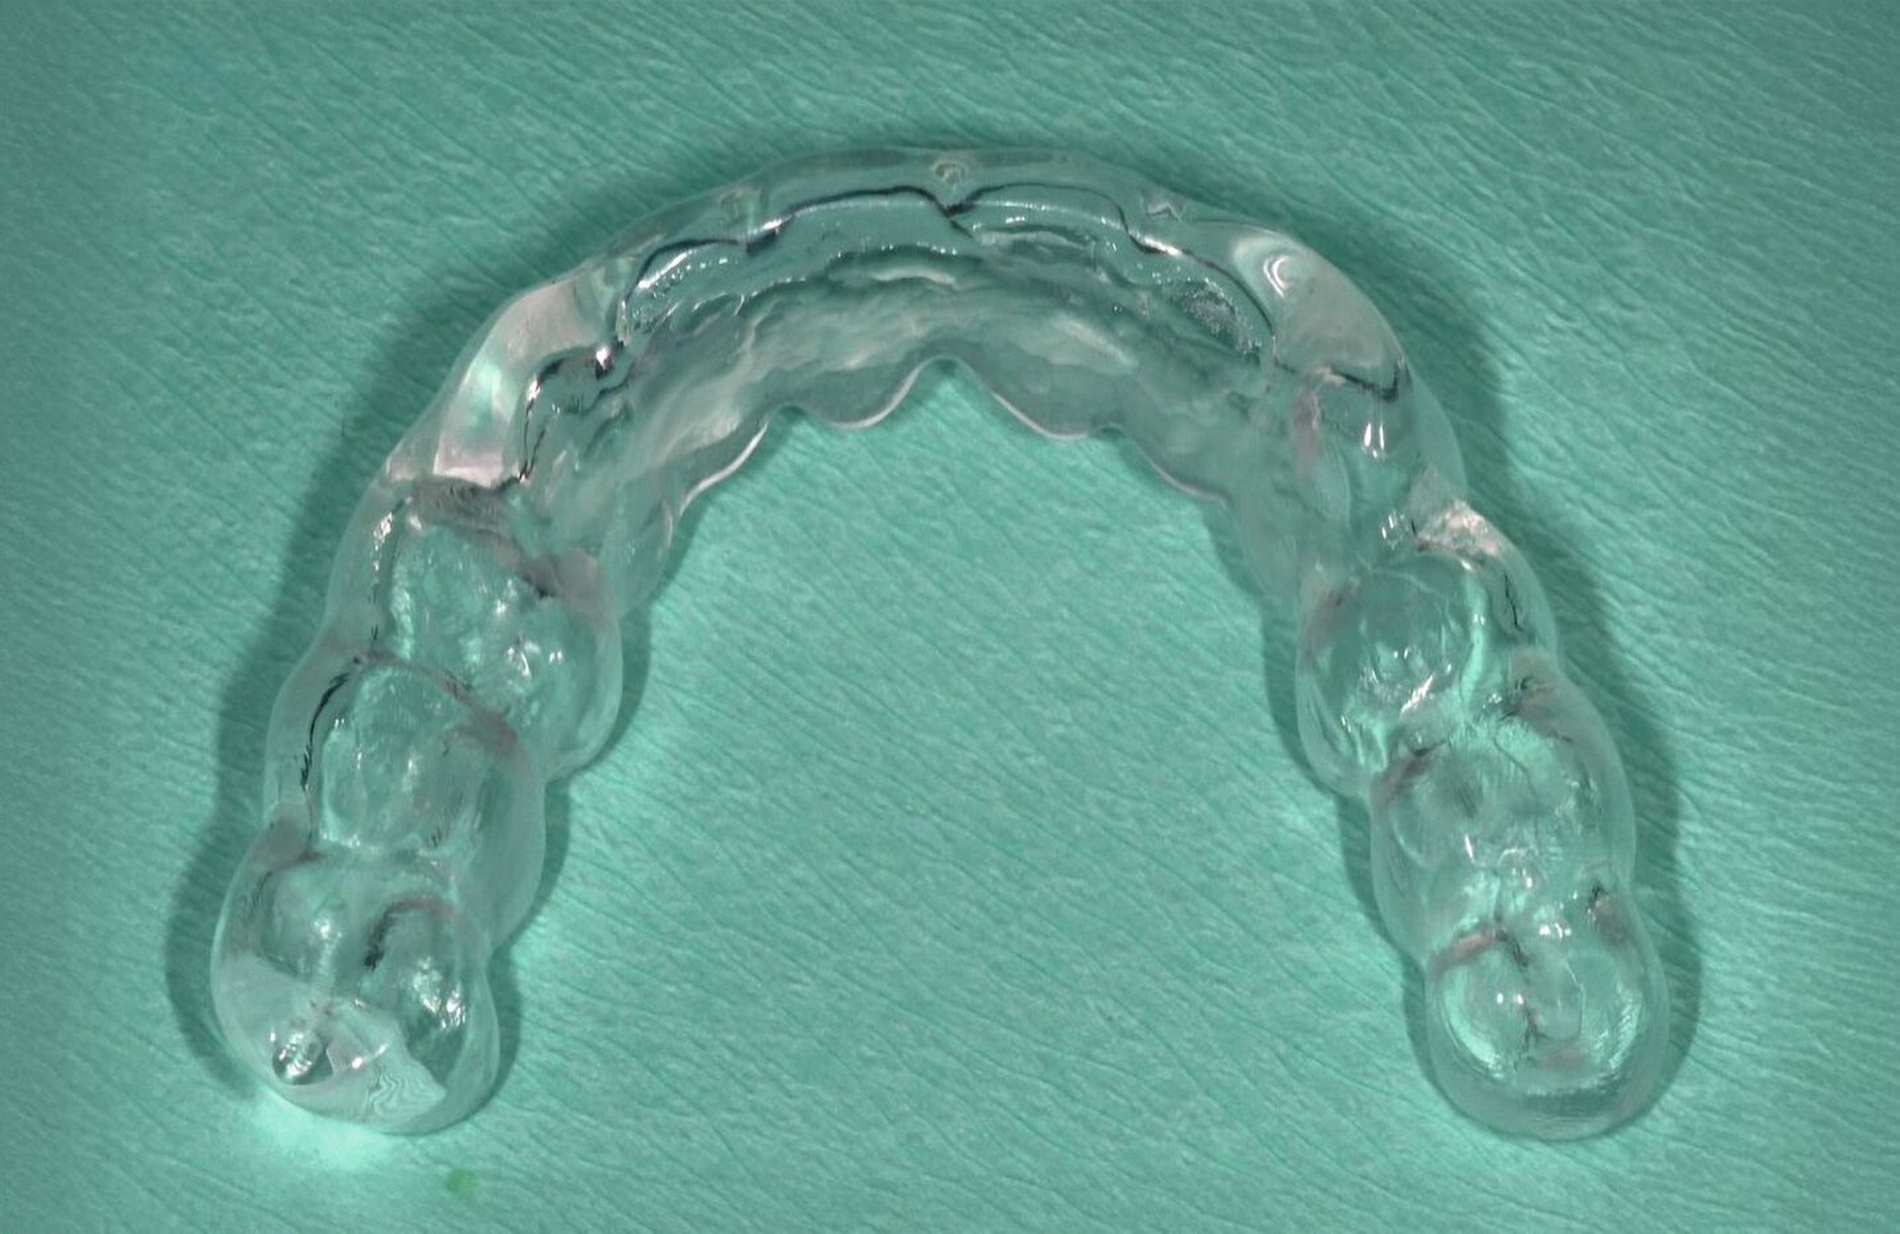

Wie kann eine Stabilisierung der kieferorthopädisch behandelten Dentition bei Patienten mit Parodontitis im Stadium IV erreicht werden?

Nach der kieferorthopädischen Behandlung kommt es häufig zu einem Rezidiv im Sinne eines Zurückkehrens der bewegten Zähne in deren Position vor der Behandlung. Dies kann ästhetische und funktionelle Folgen haben, die das Behandlungsergebnis und die Patientenzufriedenheit beeinträchtigen. Daher wird in der Regel eine Art von Retention, entweder mit herausnehmbaren oder festsitzenden Apparaturen, eingesetzt – je nach vorbestehender Fehlstellung, der Art der durchgeführten Zahnbewegungen und den Präferenzen des Patienten. Festsitzende Retentionen gelten in der Regel als besser als herausnehmbare Apparaturen, wenn es um die Verringerung von Rückfällen nach der Behandlung geht, insbesondere bei einem Engstand im Frontzahnbereich [Littlewood et al., 2016]. Gleichzeitig ist diese jedoch kurz- oder langfristig anfälliger für Retentionsversagen, kann zu mehr Plaqueansammlungen oder Zahnfleischentzündungen führen und sogar unbeabsichtigte Zahnbewegungen aufgrund der Verformung des angebrachten Drahtes zur Folge haben. Daher ist es ratsam, nach einer OT bei Patienten mit Parodontitis im Stadium IV eine festsitzende Retention gegebenenfalls mit zusätzlichen herausnehmbaren Apparaturen zu verwenden (Abbildung 11). Auch sollte ein langfristiges unterstützendes Protokoll eingeführt werden, um nicht nur die parodontale Gesundheit, sondern auch die Integrität der Retentionsapparaturen und die Stabilität der Behandlungsergebnisse zu beurteilen.

Die Evidenz dieser Empfehlung stammt aus Expertenmeinungen und aus einer retrospektiven Kohortenstudie mit 52 Patienten, die mindestens zwei Jahre nach der kieferorthopädischen Behandlung nachuntersucht wurden [Han et al., 2020]. Diese Studie ergab, dass kieferorthopädische festsitzende Retainer bei Patienten mit Parodontitis im Stadium III häufiger versagen als bei Patienten mit Parodontitis im Stadium I. Sie schloss zwar keine Parodontitis-Patienten im Stadium IV ein, doch deuten diese Ergebnisse darauf hin, dass ein höherer Schweregrad der Parodontitis mit einem häufigeren Versagen des Retainers einhergeht, so dass bei Parodontitis-Patienten im Stadium IV die Notwendigkeit häufiger Nachuntersuchungen zur Überprüfung der Integrität des Retainers hervorgehoben werden sollte.